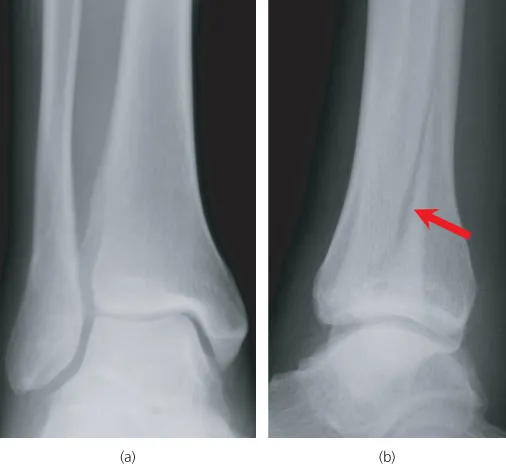

- Two views—one view is always one view too few

Rule 1—two views (‘One view is always one view too few’)